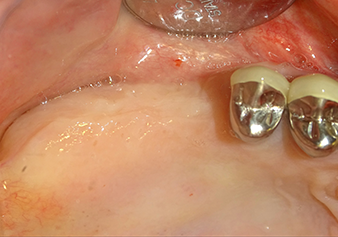

L’insert I2A (diamètre 2,0 mm) est ensuite utilisé pour perforer le plancher sinusien par intermittence et à la plus petite échelle possible. Cette méthode piézochirurgicale spéciale garantit que la membrane de Schneider n’est pas endommagée. Quand le Z25P est utilisé, la membrane est déjà légèrement relevée sous l’effet du fluide de refroidissement délivré via la pointe de l’insert (Fig. 3). Seulement 50 % du fluide de refroidissement sont éjectés afin d'éviter une pression élevée sur le site implantaire.